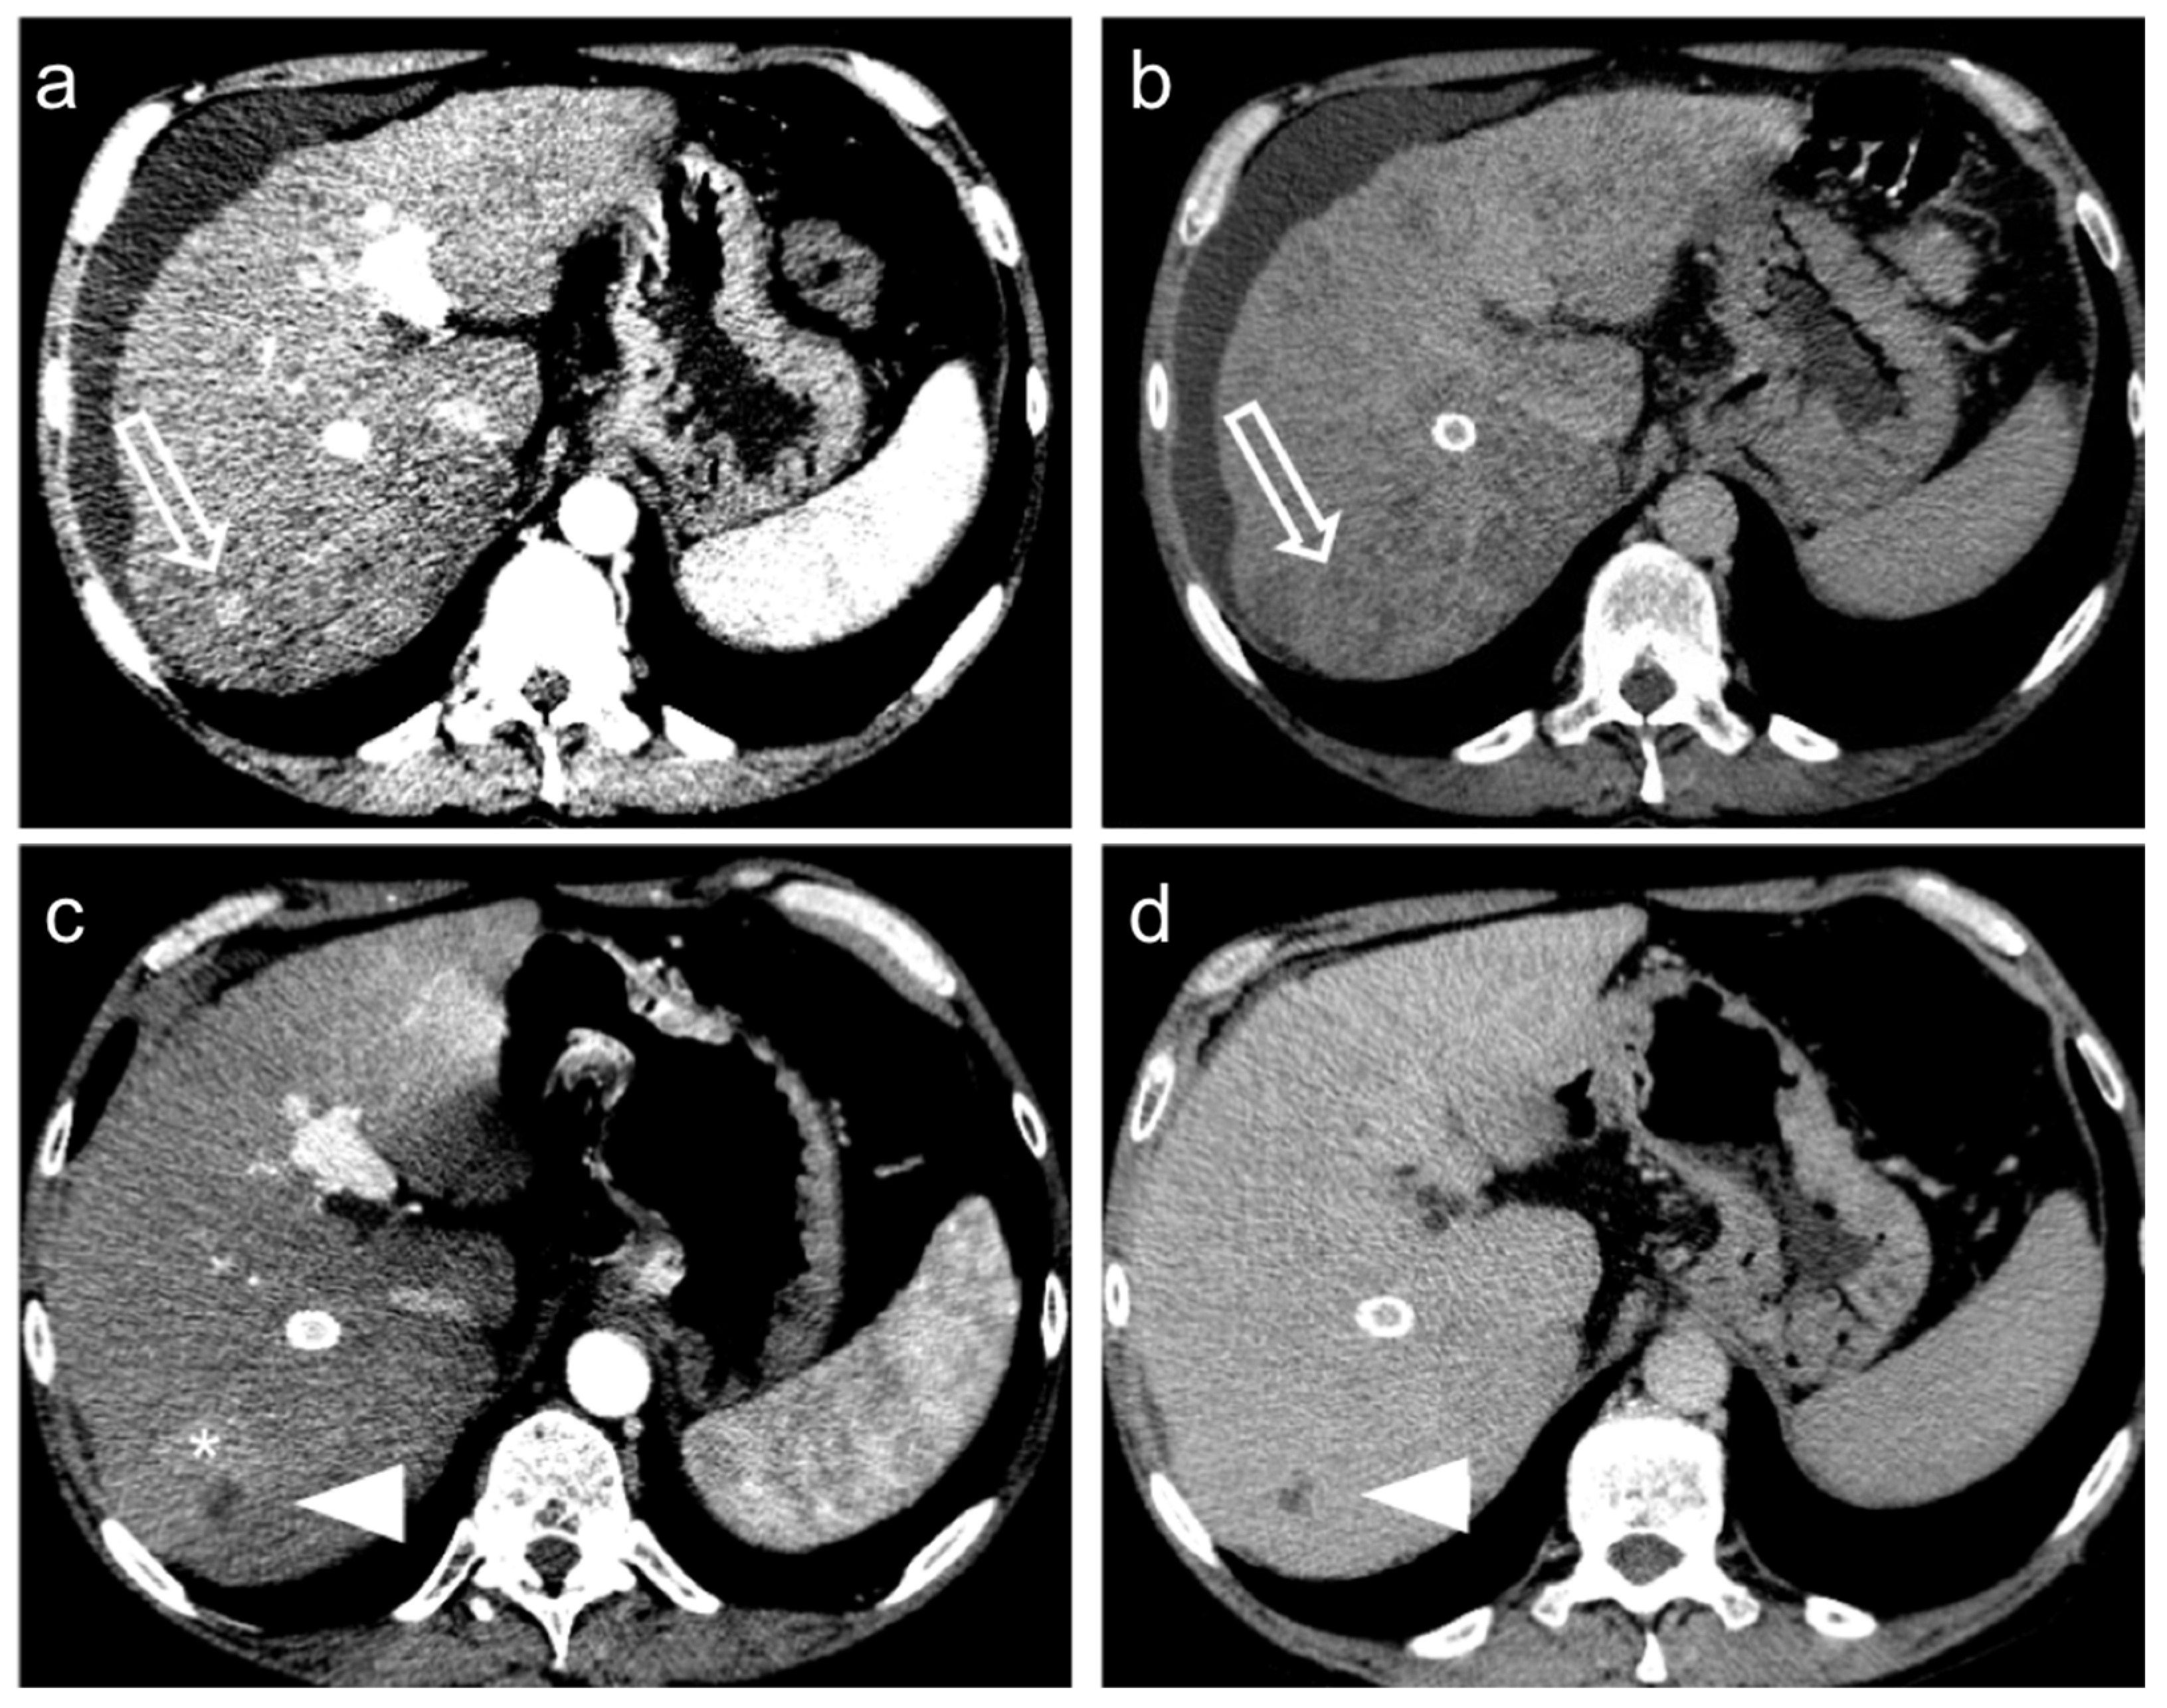

3. Treatment Response Criteria